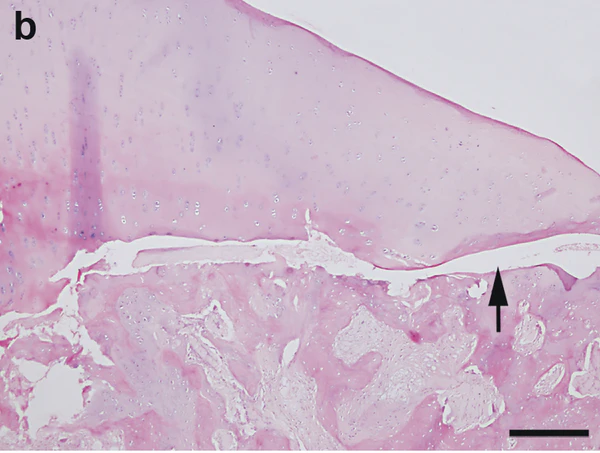

I стадия: субхондральный асептический некроз (рентгенологически не определяется). Продолжительность до шести месяцев.

На этой стадии поражается губчатое вещество при интактном хряще; рентгенологически костная патология не выявляется, поэтому при подозрении на повреждение кости необходимо проведение КТ, МРТ, денситометрии и сцинтиграфии[5].